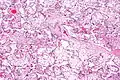

| Micrograph of villous immaturity. H&E stain. | |

Placental villous immaturity is chorionic villous development that is inappropriate for the gestational age.

Immature chorionic villi are larger and have more central blood vessels; thus, the diffusion distance for gas and nutrient exchange is larger and, therefore, placental function is impaired.

Low mag. High mag.

High mag.